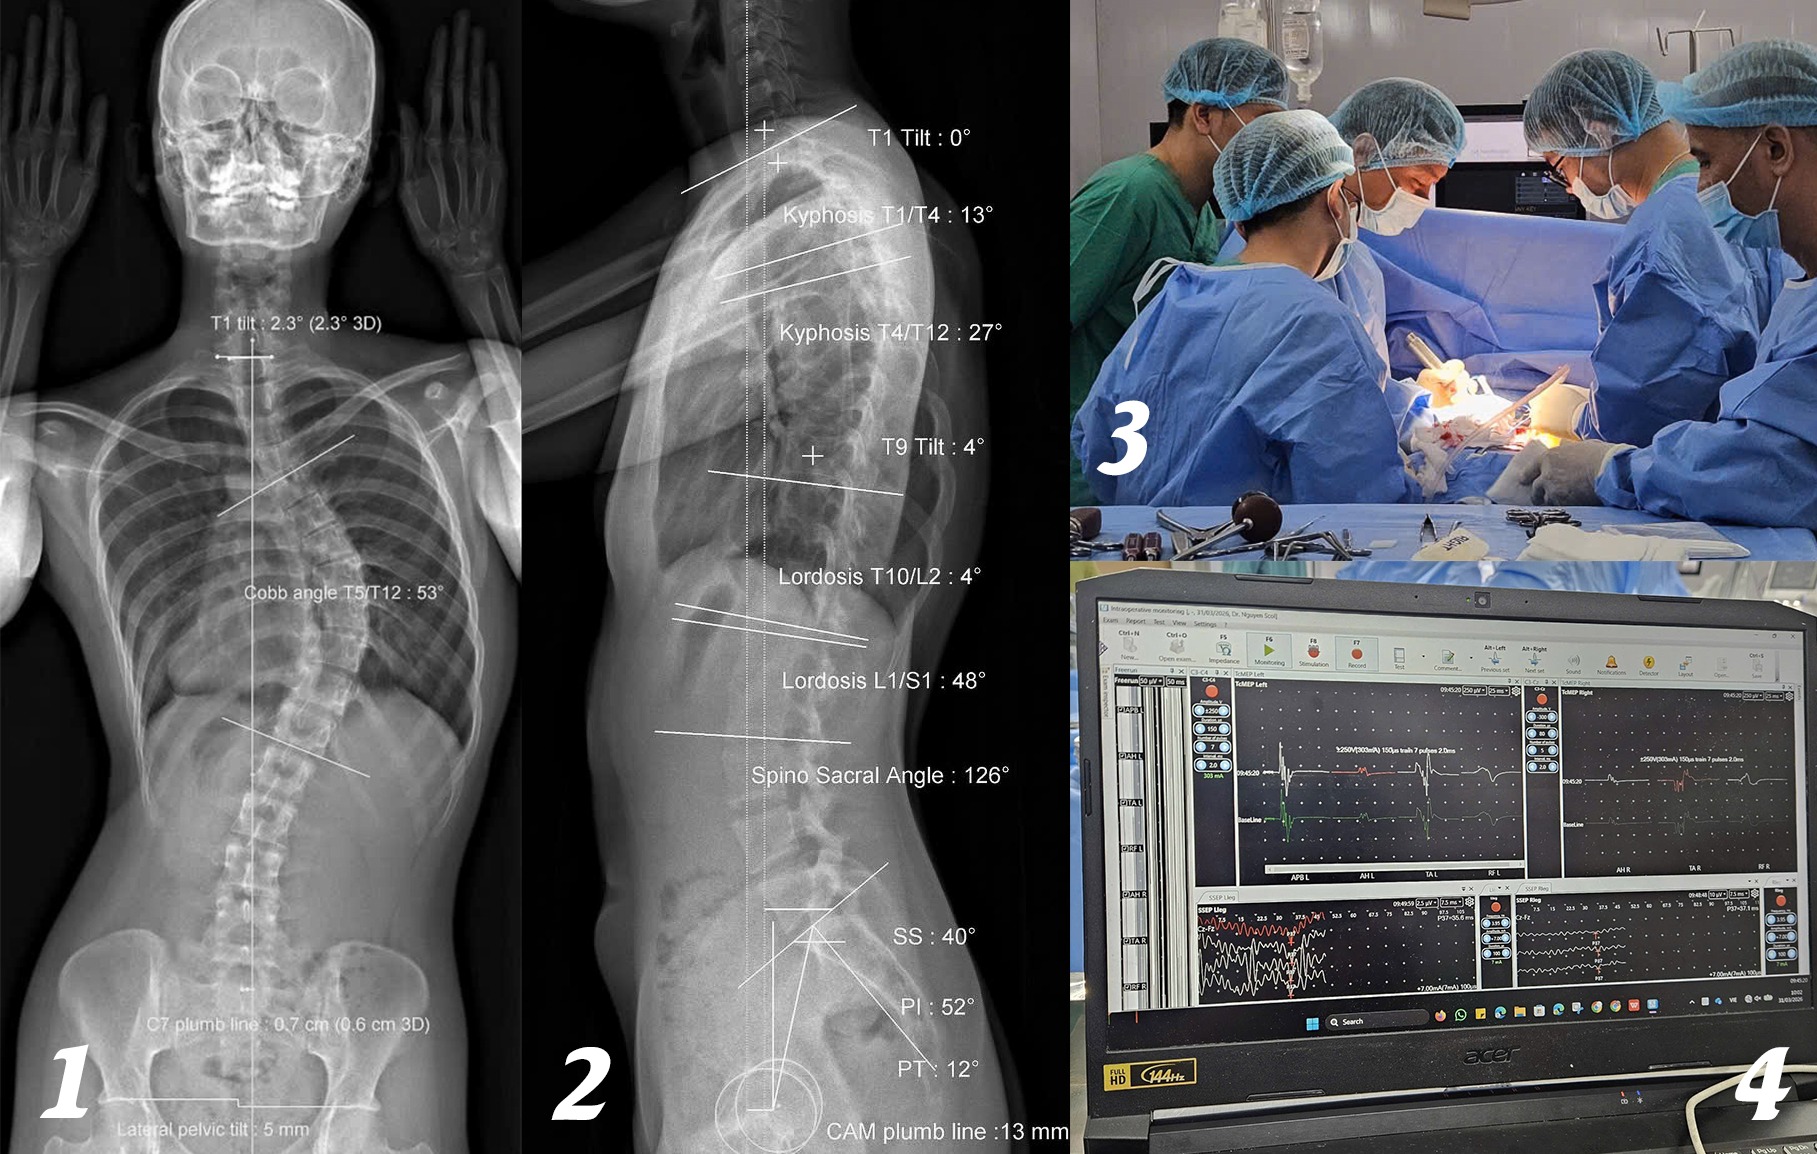

Hình ảnh EOS cho thấy người bệnh vẹo cột sống ngực 53 độ. Sau đó, các bác sĩ tiến hành phẫu thuật cùng với hệ thống IOM cảnh báo thần kinh trong phẫu thuật cột sống.

Tại đây, D. được chụp EOS (chụp quang tuyến thấy toàn bộ trục xương của cơ thể) và thăm khám. Kết quả cho thấy cột sống cô bị vẹo 53 độ, mức độ nghiêm trọng, có nguy cơ ảnh hưởng đến thẩm mỹ, tâm lý và chức năng vận động nếu không được điều trị kịp thời.

Trong quá trình phẫu thuật, các bác sĩ đã tính toán kỹ lưỡng, nắn chỉnh các đốt sống bằng hệ thống vít ốc chuyên dụng để giúp cột sống của cô trở lại mức sinh lý nhất có thể. Sau 4 giờ, ca phẫu thuật thành công.